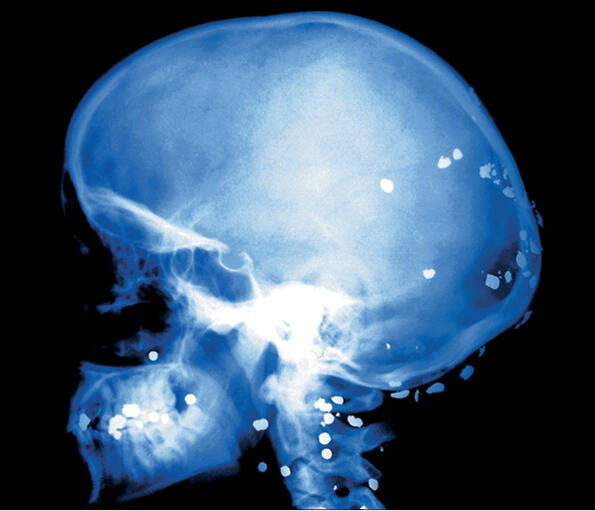

ЕКСПОНАТ 1

Пирон в главата

Южна Африка. Децата в мазето са си играли на Гестапо... За щастие това момченце няма никакви увреждания и е напълно живо и здраво.